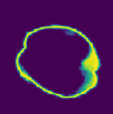

Despite the state-of-the-art performance for medical image segmentation, deep convolutional neural networks (CNNs) have rarely provided uncertainty estimations regarding their segmentation outputs, e.g., model (epistemic) and image-based (aleatoric) uncertainties. In this work, we analyze these different types of uncertainties for CNN-based 2D and 3D medical image segmentation tasks. We additionally propose a test-time augmentation-based aleatoric uncertainty to analyze the effect of different transformations of the input image on the segmentation output. Test-time augmentation has been previously used to improve segmentation accuracy, yet not been formulated in a consistent mathematical framework. Hence, we also propose a theoretical formulation of test-time augmentation, where a distribution of the prediction is estimated by Monte Carlo simulation with prior distributions of parameters in an image acquisition model that involves image transformations and noise. We compare and combine our proposed aleatoric uncertainty with model uncertainty. Experiments with segmentation of fetal brains and brain tumors from 2D and 3D Magnetic Resonance Images (MRI) showed that 1) the test-time augmentation-based aleatoric uncertainty provides a better uncertainty estimation than calculating the test-time dropout-based model uncertainty alone and helps to reduce overconfident incorrect predictions, and 2) our test-time augmentation outperforms a single-prediction baseline and dropout-based multiple predictions.